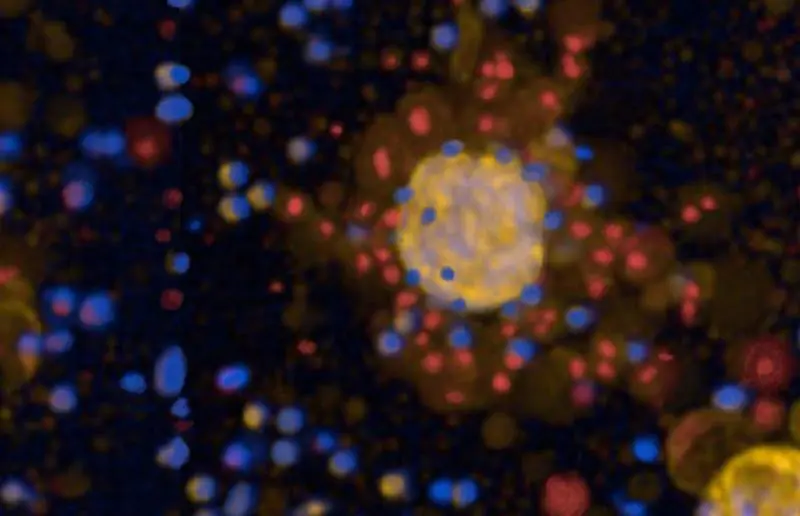

Zunächst validierten die Forscher die Tumoroide an klassischen Chemotherapien. Anschließend prüften sie die Wirksamkeit von CAR-T-Zellen, einer Immuntherapie, bei der T-Zellen genetisch modifiziert werden, um Krebszellen gezielt zu erkennen und zu zerstören. CAR-T-Zellen haben sich bei Blutkrebsarten bewährt, bei soliden Tumoren wie Lungenkrebs bleibt die Entwicklung jedoch herausfordernd. Die Tests zeigten, dass nicht nur die Häufigkeit von Zielmolekülen auf Tumorzellen entscheidet, ob CAR-T-Zellen erfolgreich wirken. Tumoreigene Schutzmechanismen und Immunfluchtstrategien spielen eine entscheidende Rolle. Gesunde Lungenorganoide dienten als Kontrolle für mögliche Nebenwirkungen.

Das BIH Center for Regenerative Therapies leitete die Arbeit. Die Tumoroide spiegeln den Patiententumor genau wider und prognostizieren Therapiereaktionen zuverlässig. Zukünftige Anwendungen könnten die Behandlungsplanung verbessern und Erfolgsraten steigern. Die Forscher betonen die Bedeutung tumoreigener Schutzmechanismen für den CAR-T-Erfolg. Das Modell könnte klinisch eingesetzt werden, um bei therapierefraktären Fällen optimale Strategien zu finden.